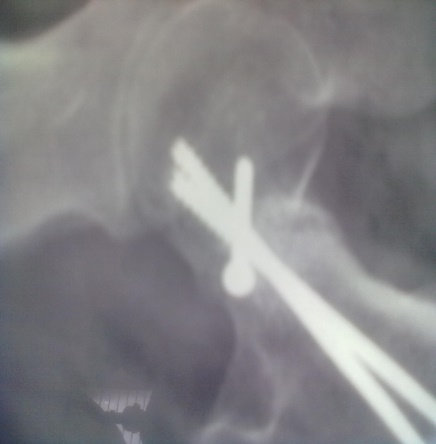

Spinal block was used in the procedure. Prone position on fracture table with radiolucent top was used. Fracture site was exposed through posterior approach and sclerosed margins of the fragments were freshened. Fracture was reduced with appropriate neck shaft angle and fixed with Moors pin/ knowels pin or 4 mm /7mm partially threaded cancellous screws. Any rotation or tilt was corrected. The fixation was augmented with quadratus femoris muscle pedicle bone graft harvested from intertochateric crest area with a bone pedicle of length 2 cm, width 1 cm and depth 1 cm. The graft was secured to the proximal femoral head fragment with 3.5mm cortical screw or 4mm cannulated cancellous screw. Soft tissue closure was done over drain.

Patients were followed up at 2 weeks, 4 weeks, 6 weeks, 8weeksk, regularly at 6 week interval for next 6 month and then at three month interval up to two year. Radiographic analysis was performed at each follow up with special attention to extent of callus formation, alignment of fragments and hard ware integrity.